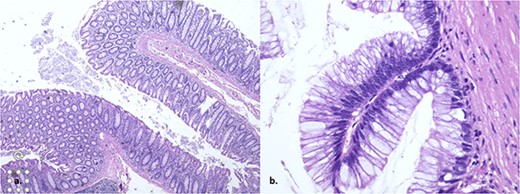

The pathology report unveils a confined low-grade appendiceal mucinous neoplasm with no rupture and clear margins (Fig. 3). The patient achieves a successful outcome with consistent monitoring and no complications following surgery.

The histopathology showed a low-grade appendiceal mucinous neoplasm with no rupture and clear margins.

Histology is crucial in determining the treatment and prognosis of appendiceal mucinous lesions [10]. The results of the histopathological analysis, in this case, showed a confined low-grade appendiceal mucinous neoplasm without rupture and with negative margins, which meant that no additional treatment was required.